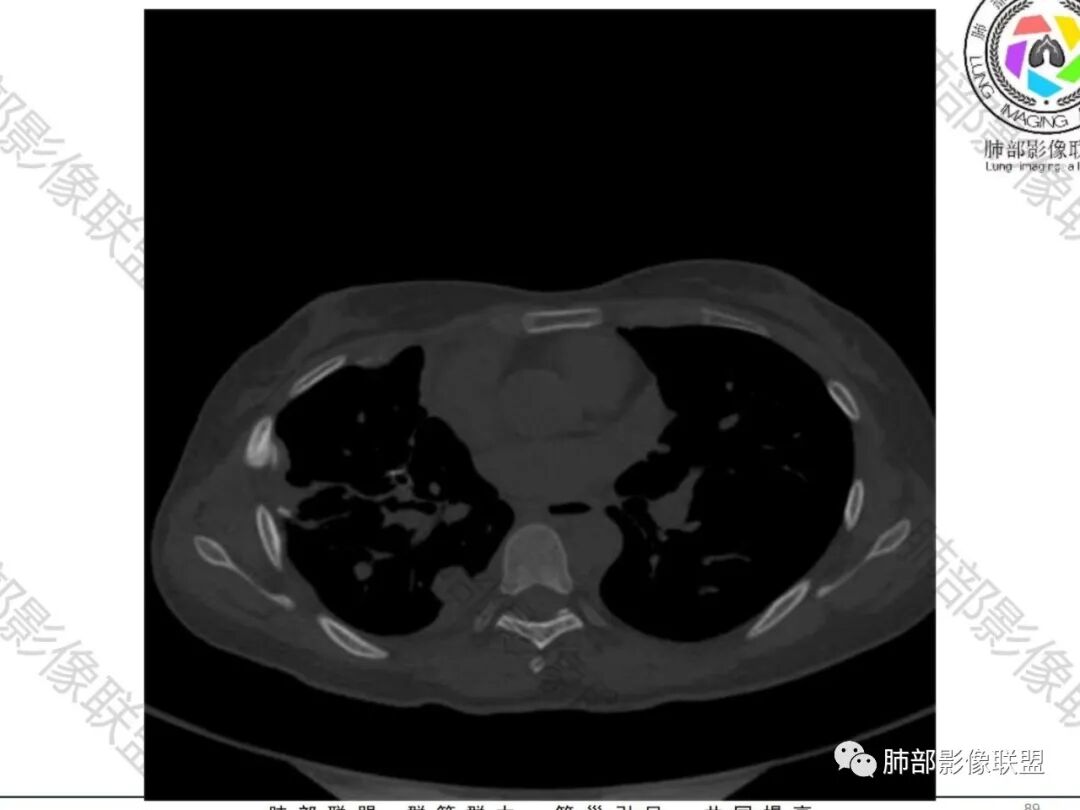

一切∮随缘:双侧胸廓塌陷,以右侧为主,右侧肋间隙狭窄,双肺上叶及右肺下叶胸膜下多发不规则肿块,密度不均匀,内部可见条片状,不规则钙化影,部分钙化不密实,双肺多发纤维索条影,似陈旧性病灶,双侧胸水,临床年轻女性,无感染症状,考虑考虑结核淀粉样变,转移性钙化,弥漫性肺骨化病。

王秀仙:双肺多发条索状及结节状病灶,部分钙化,边界清晰,双侧纵膈胸膜及双侧胸膜可见结块状及弧形软组织肿块,内见多发钙化灶,右侧胸腔塌陷,考虑结核伴淀粉样变性。鉴别胸膜间皮瘤。

丽:双肺散在索条及条片状高密度影,边界清晰,部分实变内可见钙化,支气管管壁增厚,双肺胸膜局限性增厚伴钙化,部分肋骨密度增高,首先考虑结核并淀粉样变性,鉴别转移性钙化,肿瘤样钙质沉着症,胸膜间皮瘤。

傅昌瑜:青年女性,咳嗽胸痛2月,偶有血痰。双肺上叶多发不规则肿块,密度不均匀,内部可见点状、条片状钙化影,右上肺病灶空洞,壁厚薄不均,见壁结节,与支气管关系不清,两侧胸膜增厚,见多发结节,部分结节边缘膨隆明显,结节内亦有多发钙化。上述改变常见于结核、尘肺、钙化性转移等疾病。有膨隆感的结节考虑转移可能性大。

右肺体积缩小,上叶见空洞影

内壁较光滑,但有壁结节

上叶内多个结块,边缘有膨隆,内有钙化灶

钙化灶密度较高,环形/结节状

胸膜及附近肺内见多发结节/斑块

密度类似

边缘膨隆